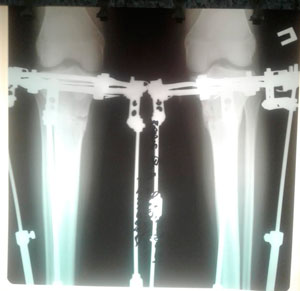

Исходник - 16 лет.

Дата оперцаии - 03.06.2019г.

Дата операции - 03.06.2019г.

Дата снятия аппаратов - 13.08.2019.

Срок сращения - 70 дней.